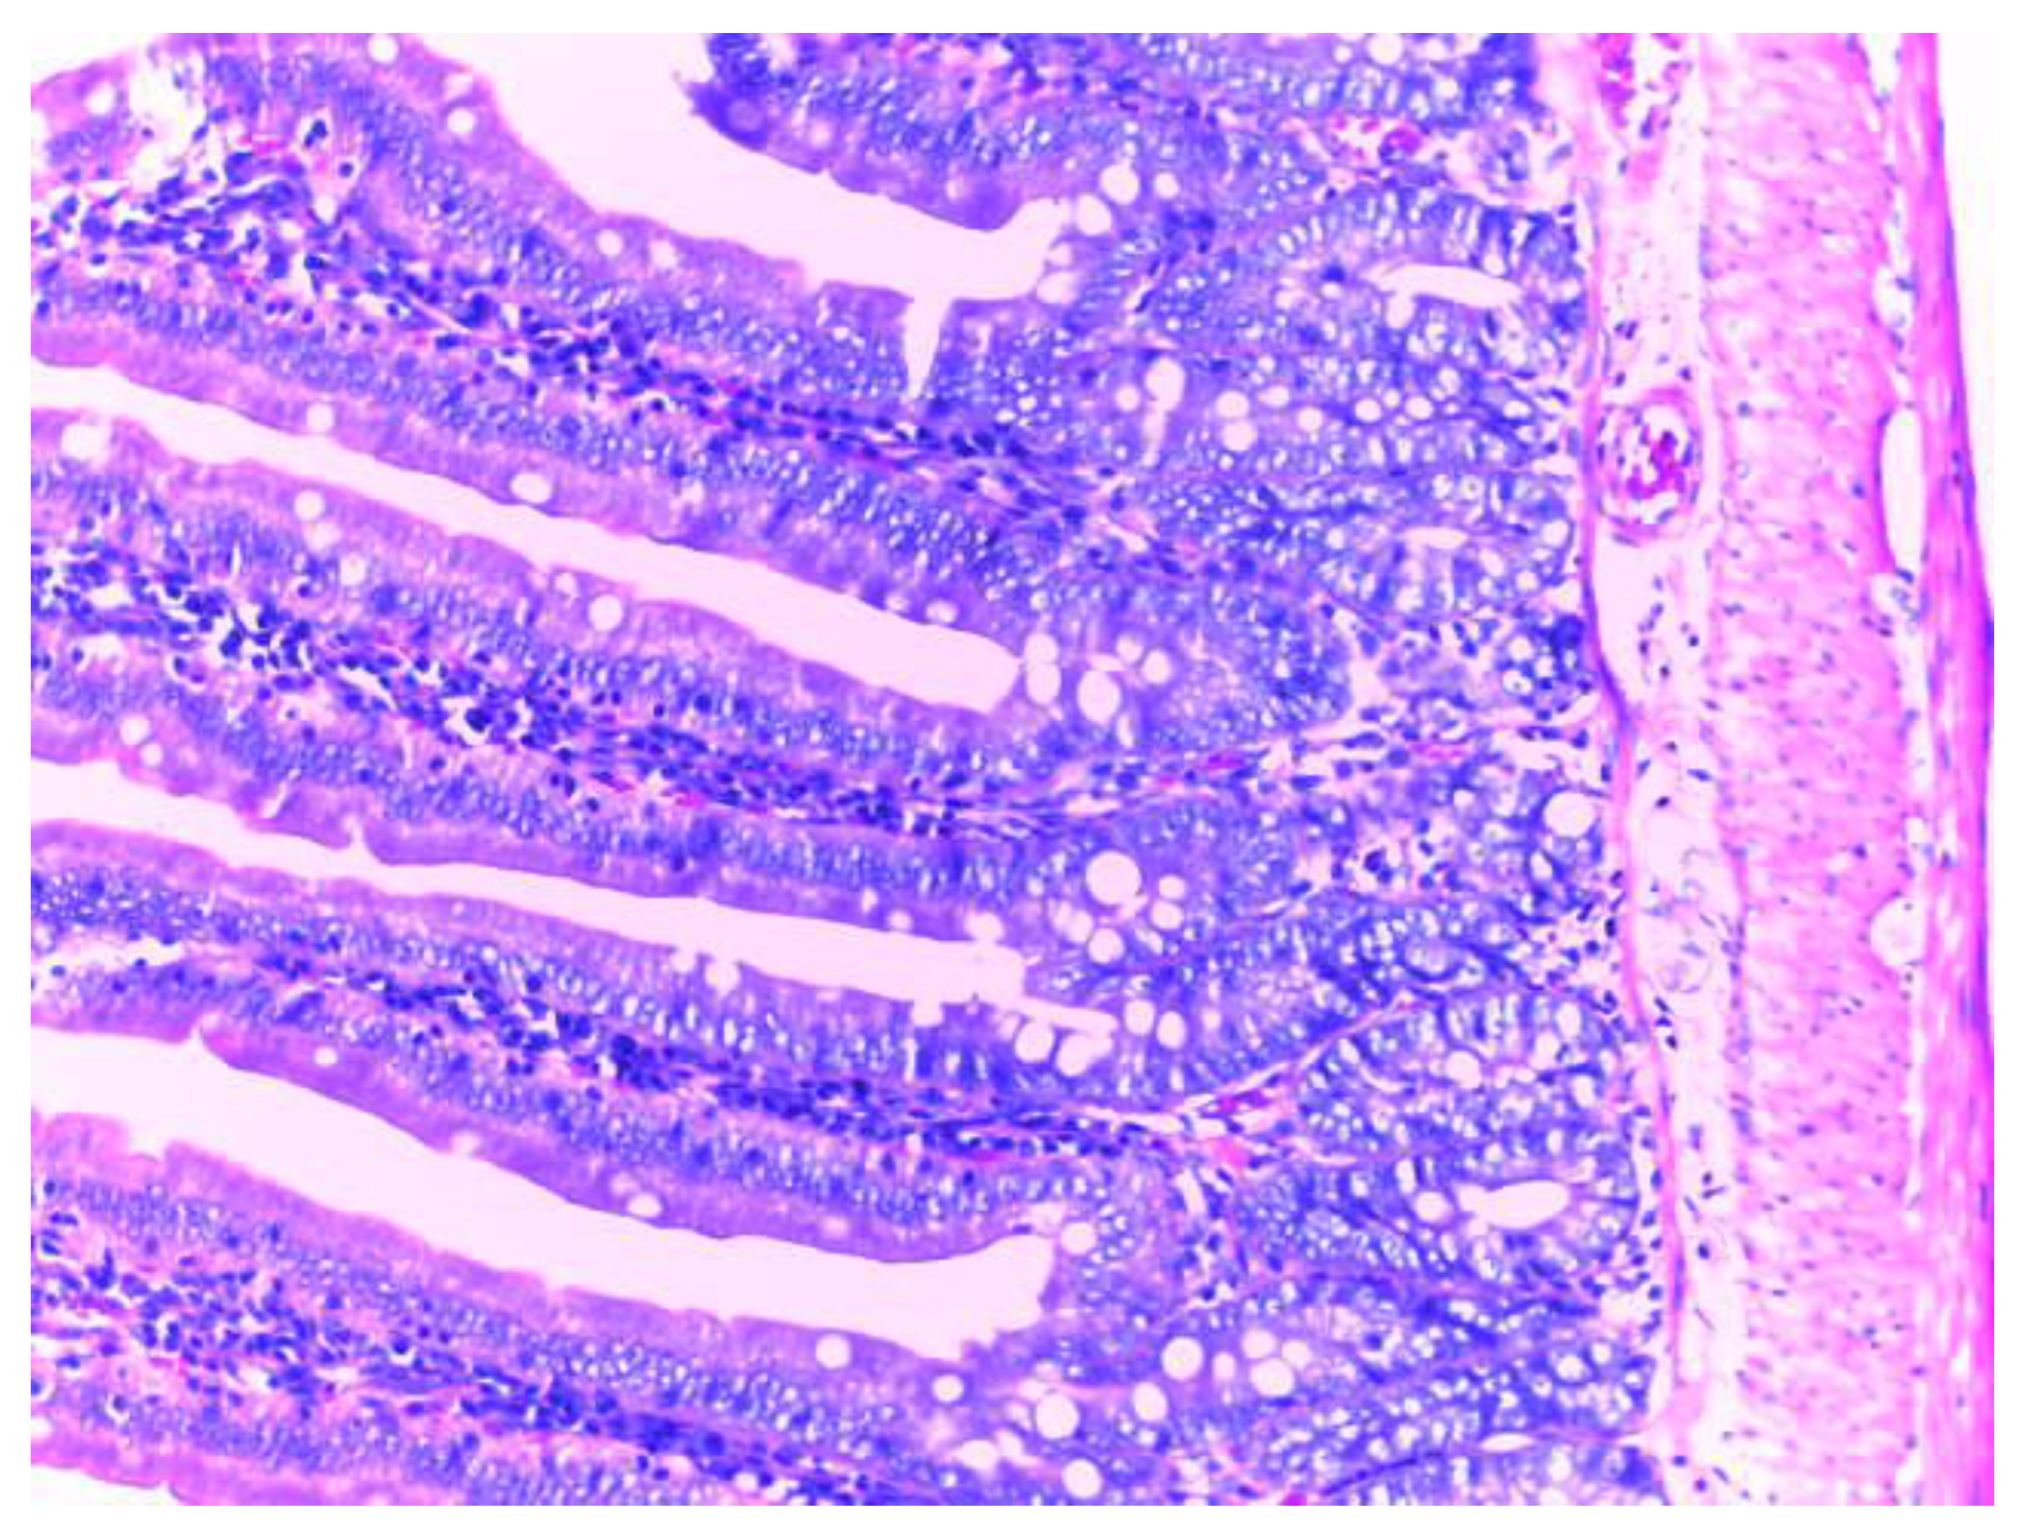

The control group (group I) shows a normal structure of the small intestine with intestinal villi, numerous simple tubular intestinal glands lined by polymorphic glandular epithelium, and lamina propria (chorion) with loose connective tissue and a discrete inflammatory infiltrate. The muscularis mucosae, submucosa, tunica muscularis and serosa have a normal histological appearance (Figure 9).

Figure 9. Normal histological appearance of the small intestine in group I (H&E stain, ob 20X).